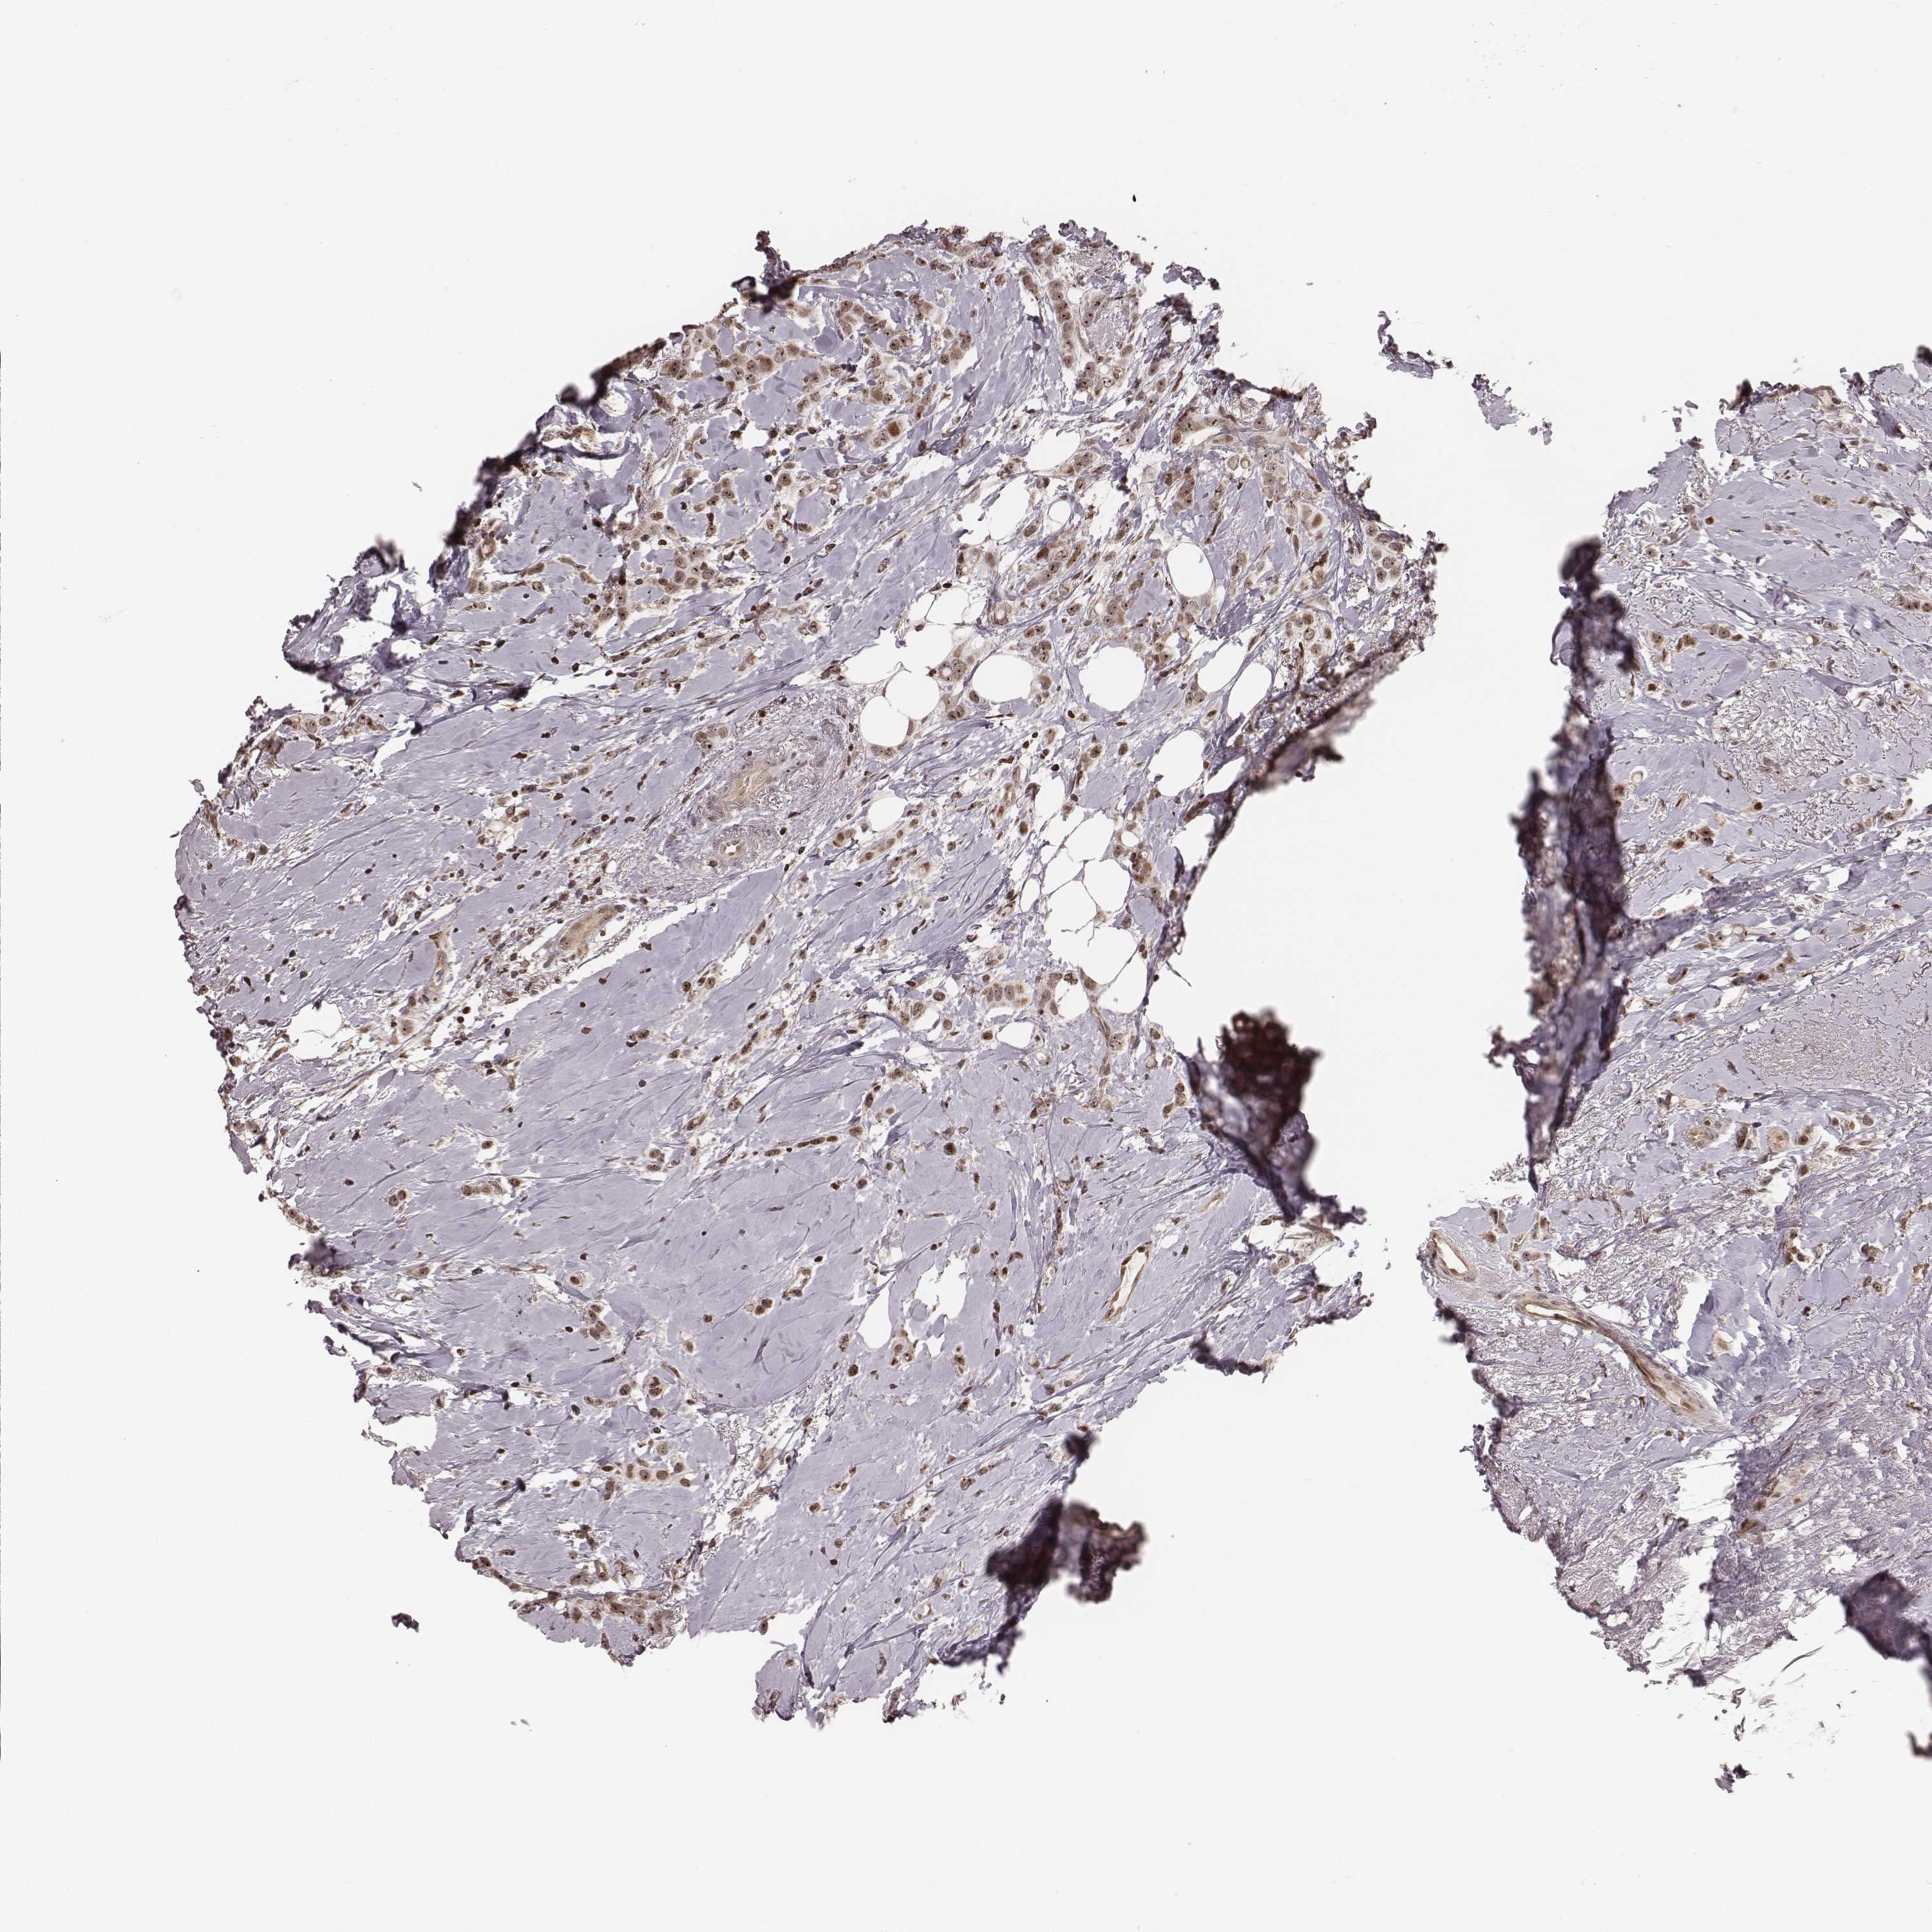

BRCA TCGA BRCA VALIDATION PROTEIN EXPRESSION